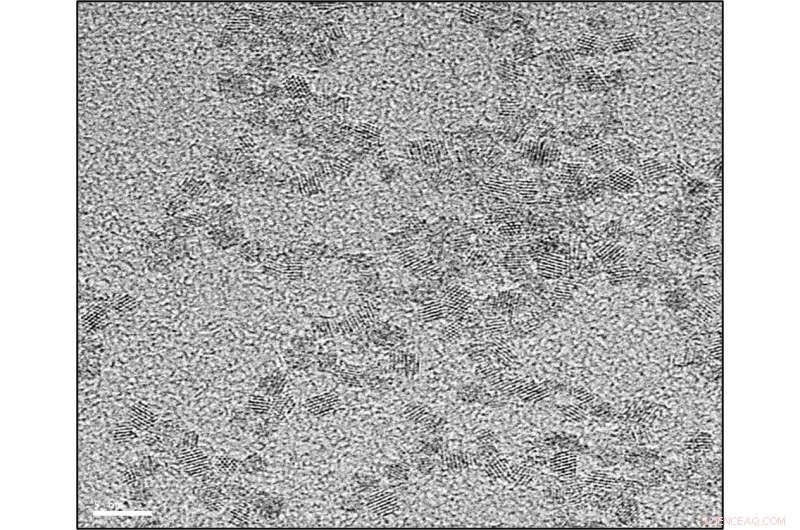

Cerium oxide nanoparticles nanoparticles. Credit: Catalan Institute of Nanoscience and Nanotechnology

The research team injected the rats with four doses of cerium oxide nanoparticles, two per week, 16 weeks after they developed liver cancer. The spherically shaped nanoparticles, between 4 and 20 nanometers, were mainly concentrated in the liver and spleen a few days after administration. The treated rats attenuated the number of cancer nodules in the liver, had reduced levels of the cancer biomarker alpha-fetoprotein, showed less proliferation of the cancer cells and more apoptosis cell death, and had beneficial effects by reducing the damage produced by inflammation and altered lipid metabolism. When the survival of the treated rats was compared, it was observed that both the nanoparticles and the best therapeutic option available at the time of the study doubled the survival of the rats from about 15 days to over 30.